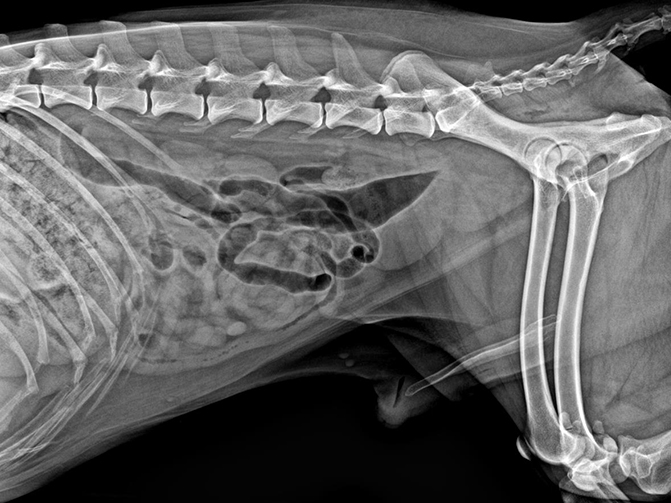

02

VET-528